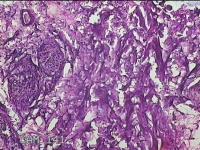

头枕部包块

性别

男

年龄

47岁

临床诊断

一般病史

发现头枕部包块10年余。

标本名称

大体所见

灰白暗红色组织4.3x2.5x1.2cm一块,表面带梭形皮肤4.3x1.7cm,皮下见包块3x1.8cm一个,切开包块呈实性,切面灰白淡黄色,质软。

图2